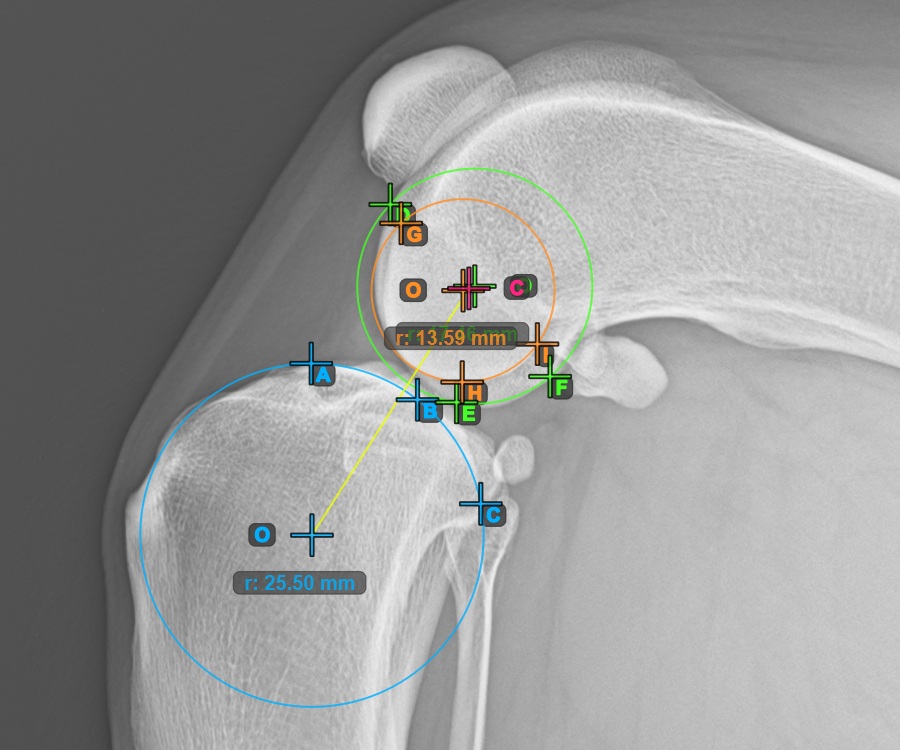

Jelölje meg a három pontot a combcsont belső (másodlagos) condylusán (Condylus Femoris). A sorrendtől függetlenül ügyeljen arra, hogy megjelölje a legfelső pontot, a legalacsonyabb pontot és a Condylus Femoris középpontját. A három pont alapján a rendszer automatikusan létrehoz egy kört.

A lenti kép a második Condylus Femoris-on elhelyezett három pont tipikus elhelyezkedését ábrázolja.